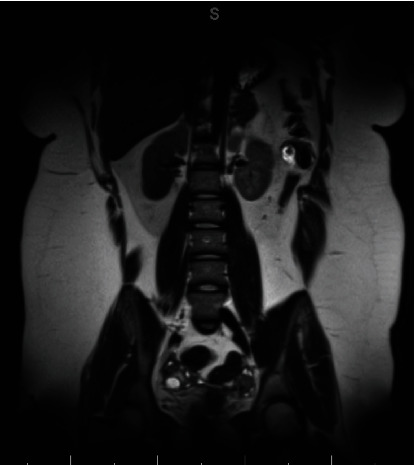

Background: Anti-NMDA receptor (A-NMDAR) encephalitis is an autoimmune condition often associated with ovarian teratoma. Surgical removal of the teratoma is generally curative, and recurrence is uncommon. Case: A 14-year-old female presented with psychiatric symptoms and was ultimately diagnosed with A-NMDAR encephalitis during a prolonged hospitalization. She was found to have bilateral ovarian teratomas, underwent laparoscopic bilateral ovarian cystectomy, and returned to neurologic baseline within 2 months. One year later, the patient was re-presented with similar symptoms and was diagnosed with recurrent A-NMDAR encephalitis. Initial imaging was negative for ovarian teratomas. After another prolonged hospitalization, repeat imaging ultimately demonstrated a suspected left ovarian teratoma. A left salpingo-oophorectomy was performed, and the patient's condition again fully recovered. Conclusion: This case of A-NMDAR encephalitis presented with many atypical features including neuropsychiatric presenting symptoms, bilateral teratomas, and severe recurrence of disease. While imaging is the recommended modality for investigation of etiology, no teratoma was identified on the second presentation, leading to an ethical and clinical conundrum in this adolescent patient. More research is needed to investigate other diagnostic methods for A-NMDAR encephalitis without distinct teratoma on imaging in female patients.

Abstract Image